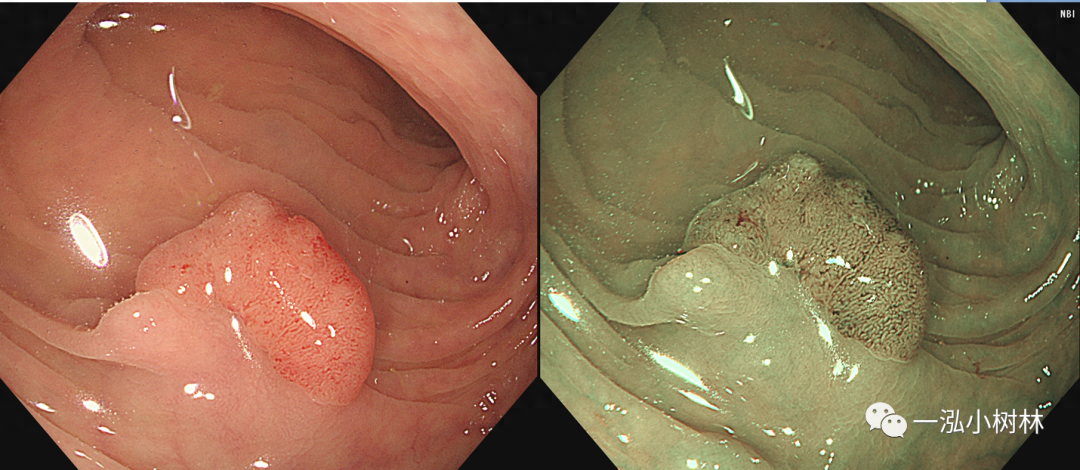

图3 结肠管状腺瘤(Pit Pattern IIIL型)